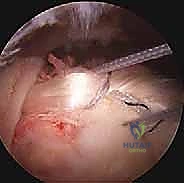

يبدأ الدكتور هطيف بالاستماع بعناية لتاريخ المشكلة: متى بدأ الألم؟ ما هي الأنشطة التي تزيده؟ هل هناك إصابة سابقة؟ بعد ذلك، يتم إجراء فحص سريري دقيق يتضمن اختبارات ميكانيكية متخصصة مصممة خصيصاً لاستفزاز وتر العضلة ذات الرأسين وتحديد مدى تضرره، مثل:

* اختبار سبيد (Speed's Test): يطلب من المريض رفع ذراعه الممدودة للأمام ضد مقاومة الطبيب. الألم في مقدمة الكتف يشير إلى إيجابية الاختبار.

* اختبار ييرغاسون (Yergason's Test): يقاوم المريض محاولة الطبيب لقلب ساعده للخارج بينما الكوع مثني بزاوية 90 درجة. هذا يختبر استقرار الوتر داخل الأخدود العظمي.